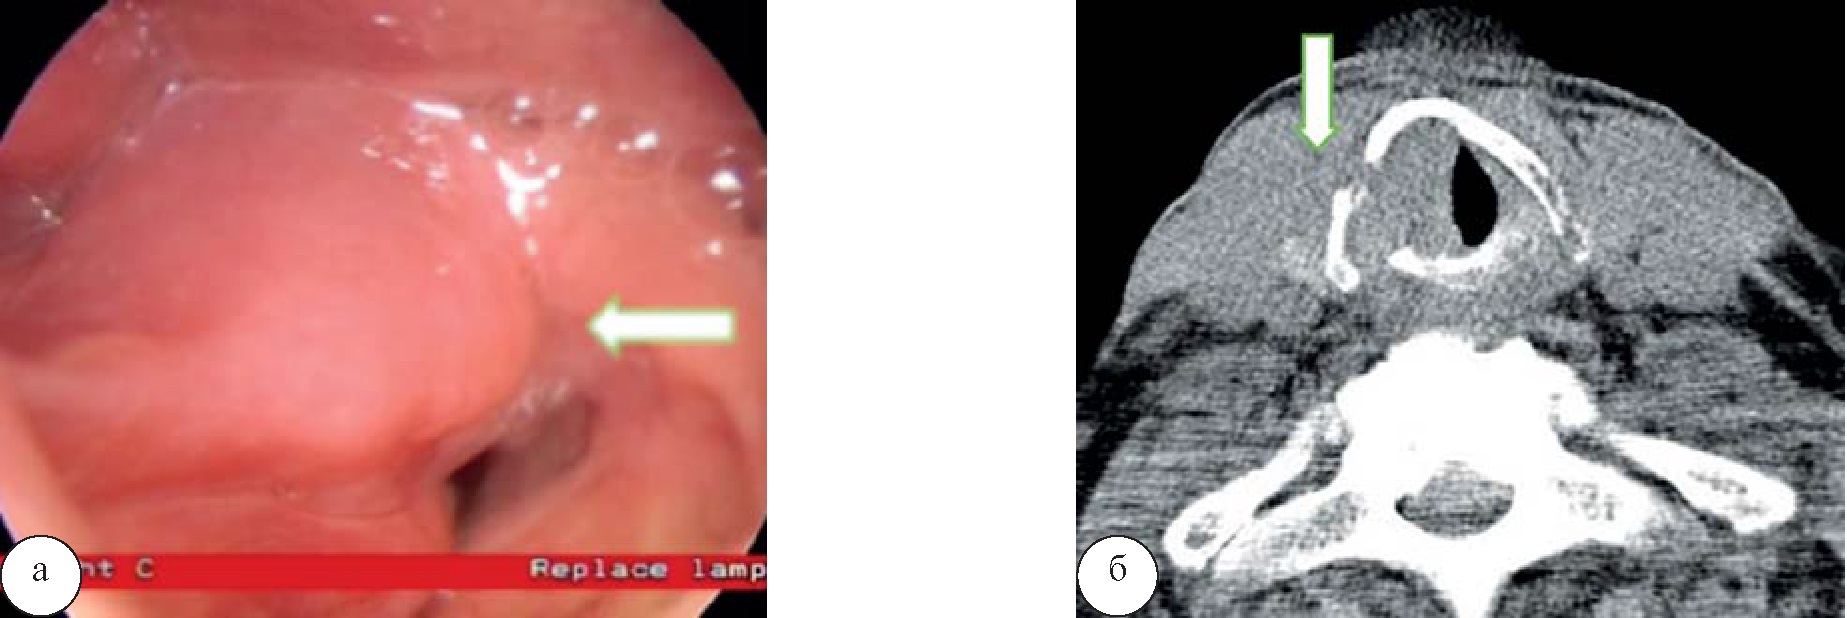

Результаты и их обсуждение. При выполнении КТ у 50 (92,5%) человек было выявлено первичное образование, в половине случаев без визуализации четкого внутреннего его контура (46,2%). У 49 (90,7%) пациентов визуализировалось накопление контрастного вещества образованием, у 10 (18,5%) человек отмечалась инвазия в прилежащие мягкие ткани, у 4 (7,4%) пациентов – деструкция хрящей гортани (рис. 1), регионарные метастазы в шейные лимфатические узлы прослеживались у 29 (53,7 %) человек.

Рис. 1. Рак гортани. При ларингоскопии (а) отмечается крупное образование правой половины гортани (стрелка). При компьютерной томографии (б) определяется крупное мягкотканное образование правой половины гортани без четких контуров, инфильтрирующее правую голосовую складку с распространением на переднюю и заднюю комиссуру, инфильтрирующее прилежащие мягкие ткани справа, вызывающее деструкцию щитовидного, перстневидного и правого черпаловидного хрящей